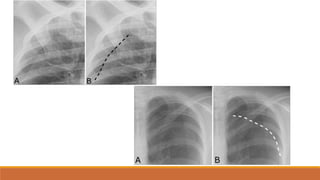

Hít đủsâu

‐Cung sau xương

sườn 10 nằm trên

vòm hoành (P)

Hít không đủ

sâu

-

‐Các mạch máu phổi

sẽ bị dồn ép lại đặc

biệt là vùng đáy phổi

Nhầm với viêm

thùy dưới phổi

Hình cân xứng

‐Khoảng cách từ

đầu trong xương

đòn đến mỏm gai

đốt sống ngực hai

bên bằng nhau

Khi hình bịxoay